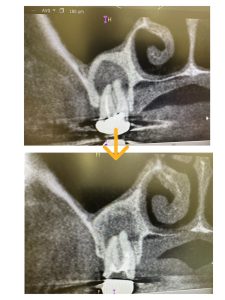

病巣改善❗️

非常に良く治ってきている!

あの秘密兵器とやり方のお陰ですよ💪

寛チャンメソッド🤪秘密だよ〰︎ん

画像みれば分かるが、骨化が著しい、次回MTA根充

寛くんメソッドは間違いない!🤪